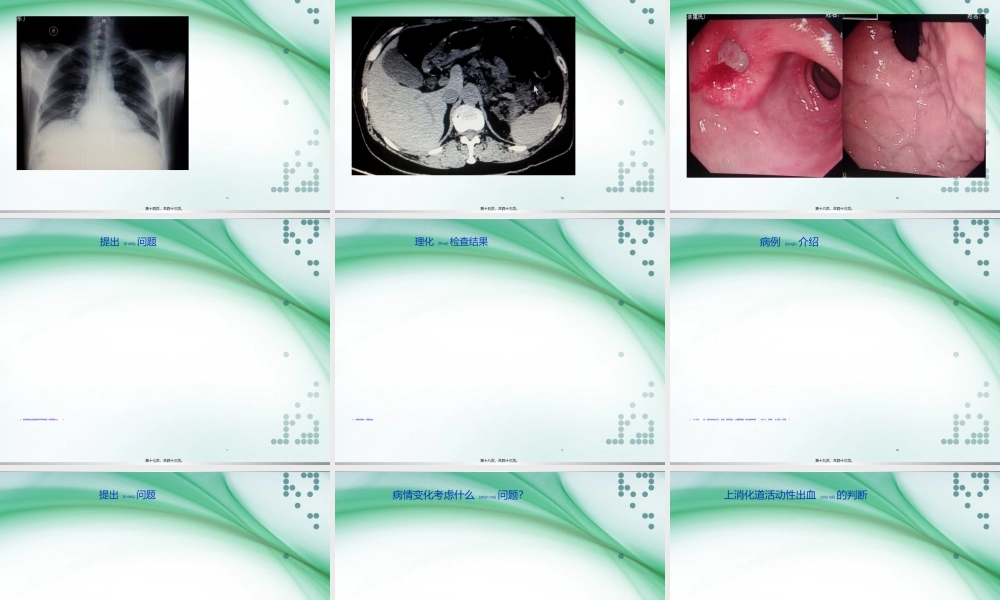

1上消化道出血(chūxiě)PBL教学第一页,共四十三页。Companyname2掌握上消化道出血的病因11掌握上消化道出血的掌握上消化道出血的临床表现临床表现22掌握上消化道出血的掌握上消化道出血的鉴别诊断鉴别诊断33掌握上消化道出血的治掌握上消化道出血的治疗疗44第二页,共四十三页。3病例(bìnglì)介绍第三页,共四十三页。4提出(tíchū)问题1、作为接诊医师,还需进一步采集那些病史。第四页,共四十三页。5病例(bìnglì)介绍1、现病史(bìnɡshǐ):1周前无明显诱因出现上腹部饥饿样疼痛不适,间歇性发作,每于上午10时、下午4时左右出现,进食后可缓解。伴反酸、嗳气、无呕吐。未行治疗。昨天开始解黑色柏油样便3次,量约800ml。伴头晕、体软。无晕厥。第五页,共四十三页。6提出(tíchū)问题1、目前初步诊断是什么疾病?第六页,共四十三页。7初步(chūbù)诊断1第七页,共四十三页。8是否(shìfǒu)为消化道出血的识别1、与鼻出血、拔牙或扁桃体切除而咽下血液所导致。第八页,共四十三页。9需完善的理化(lǐhuà)检查、血常规第九页,共四十三页。10血常规第十页,共四十三页。11血生化(shēnɡhuà)第十一页,共四十三页。12大便(dàbiàn)常规+潜血第十二页,共四十三页。13心电图第十三页,共四十三页。14胸片第十四页,共四十三页。15腹部(fùbù)CT第十五页,共四十三页。16胃镜图片(túpiàn)第十六页,共四十三页。17提出(tíchū)问题1、该患者的血液检查有何异常发现?原因是什么?第十七页,共四十三页。18理化(lǐhuà)检查结果1、血常规报告:重度贫血第十八页,共四十三页。19病例(bìnglì)介绍124小时后,突发全身出冷汗、头晕、面色苍白、上腹部疼痛、呕吐咖啡样液36.6℃、脉搏:次每分、呼吸:/。第十九页,共四十三页。20提出(tíchū)问题1、该患者目前的病情变化考虑什么问题?第二十页,共四十三页。21病情变化考虑什么(shénme)问题?1、患者出现活动性大出血。第二十一页,共四十三页。22上消化道活动性出血(chūxiě)的判断1、持续呕血或便血第二十二页,共四十三页。23估计(gūjì)患者的出血量1----------50ml以上;呕血以上。第二十三页,共四十三页。24如何(rúhé)定义为上消化道大出血3小时内需输血1500ml第二十四页,共四十三页。25如何判断患者的出血(chūxiě)部位1、消化道出血常以指屈氏韧带为界分为上消化道和下消化道,上消化道出血包括食管、胃、十二指肠、胆道和胰腺的出血。第二十五页,共四十三页...

二年级数学下册期末质检卷(苏教版)二年级数学下册期末质检卷(苏教版)#期末复习 #期末测试卷 #二年级数学 #二年级数学下册#关注我持续更新小学知识.pdf

10.00金币

0下载